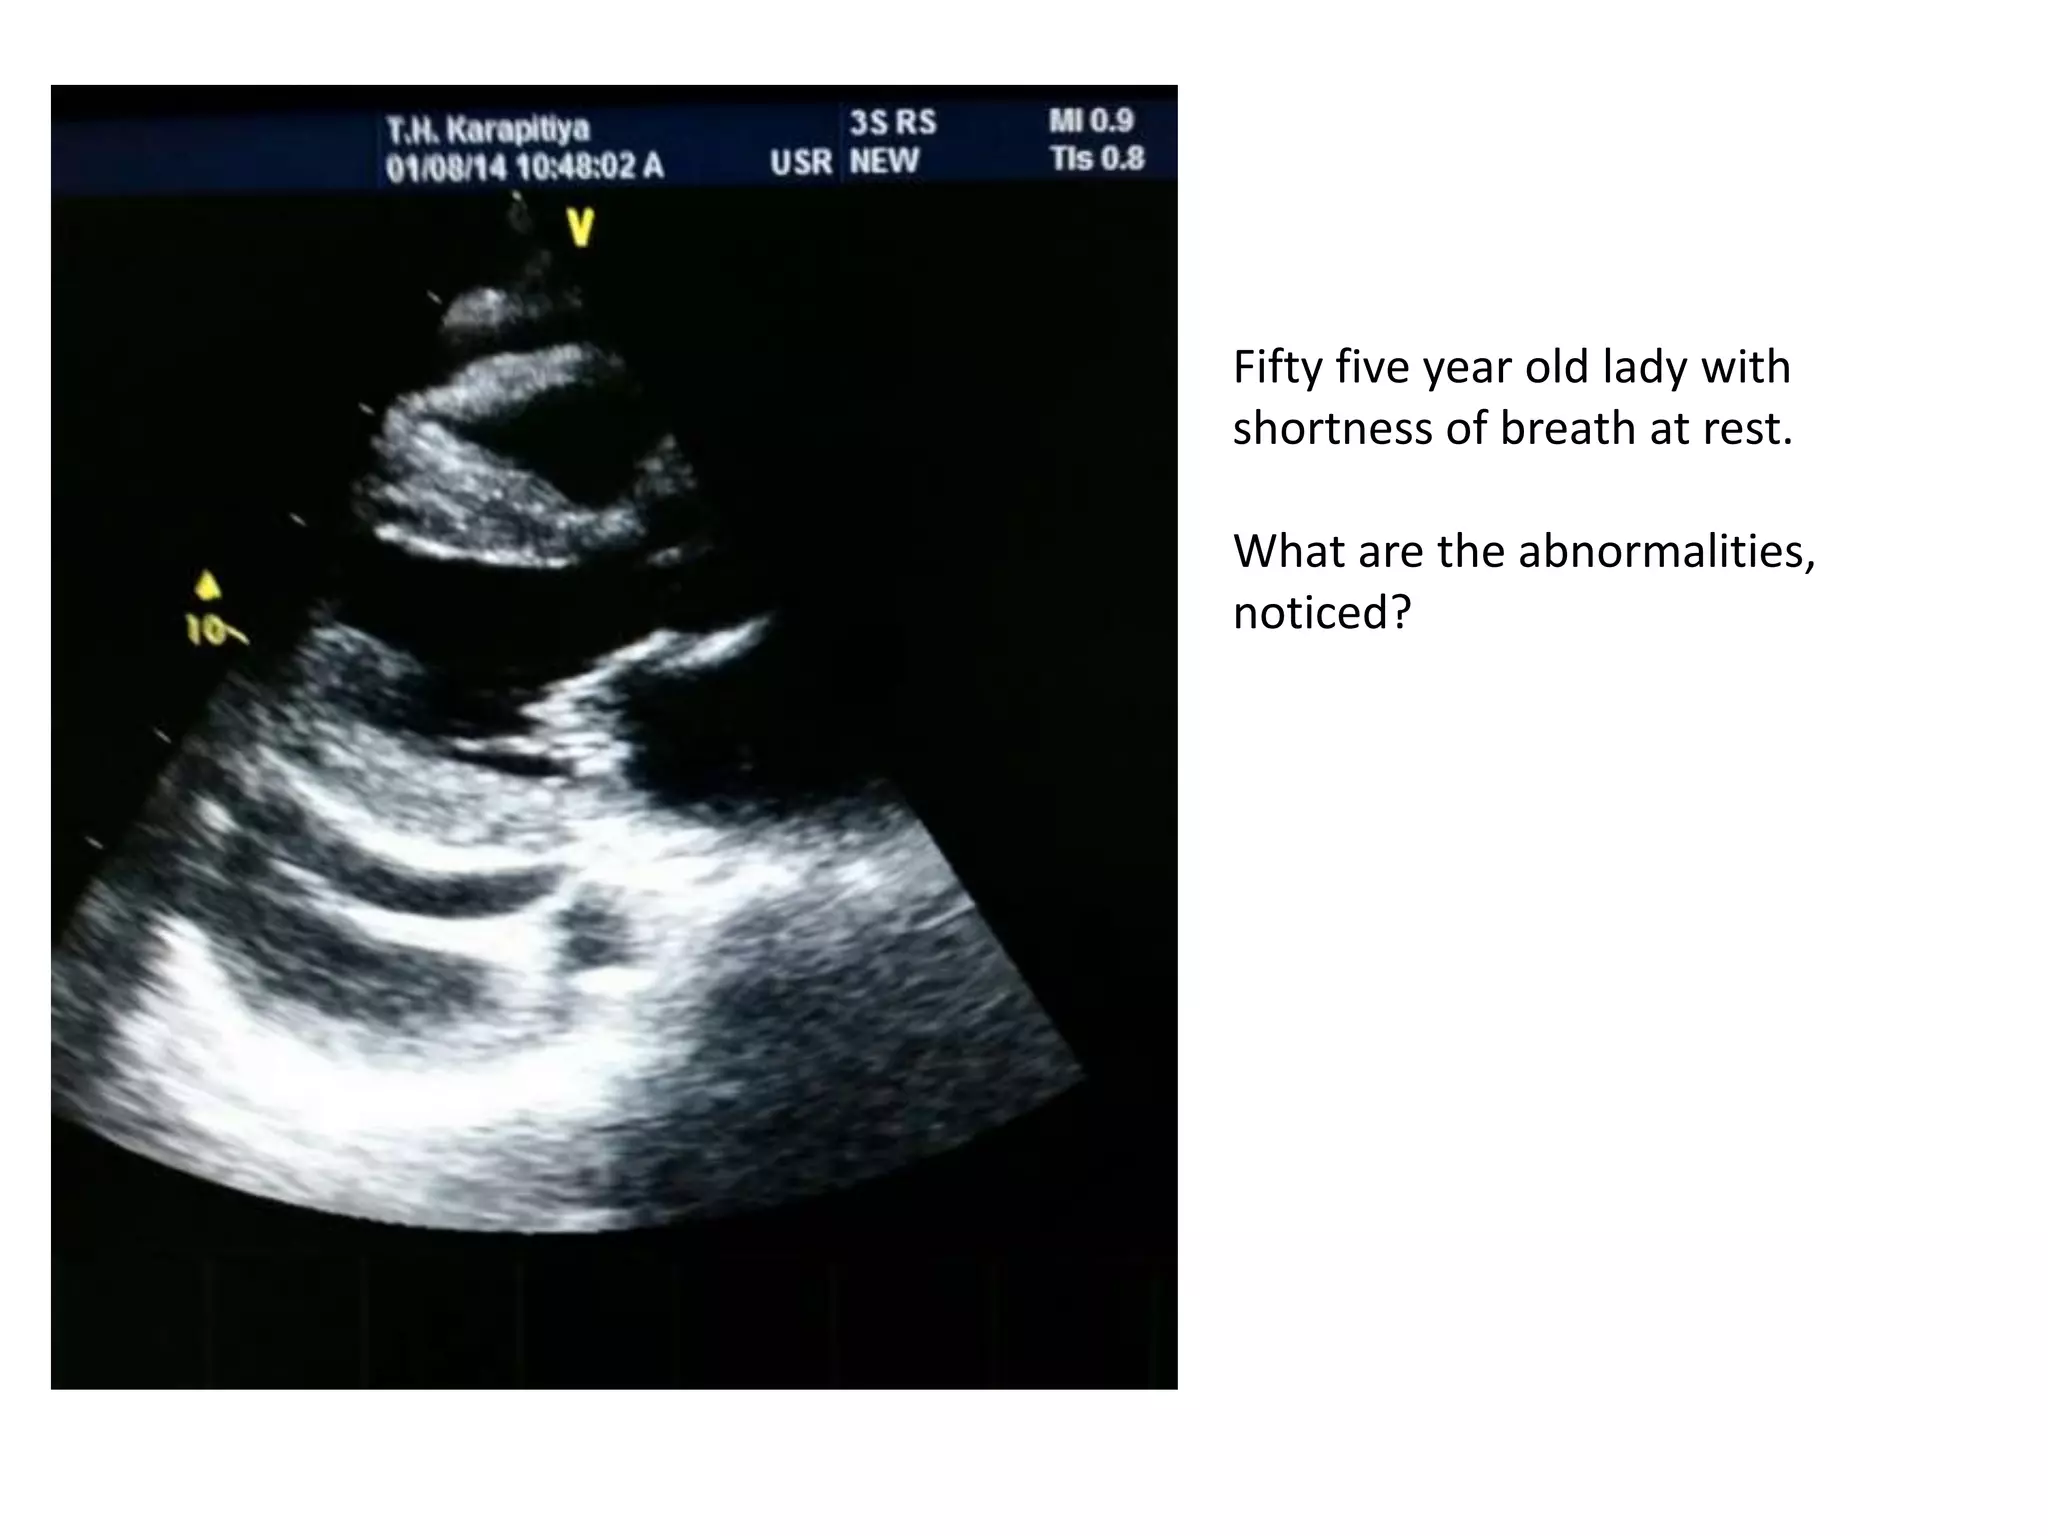

Fifty five year old lady with

shortness of breath at rest.

What are the abnormalities,

noticed?